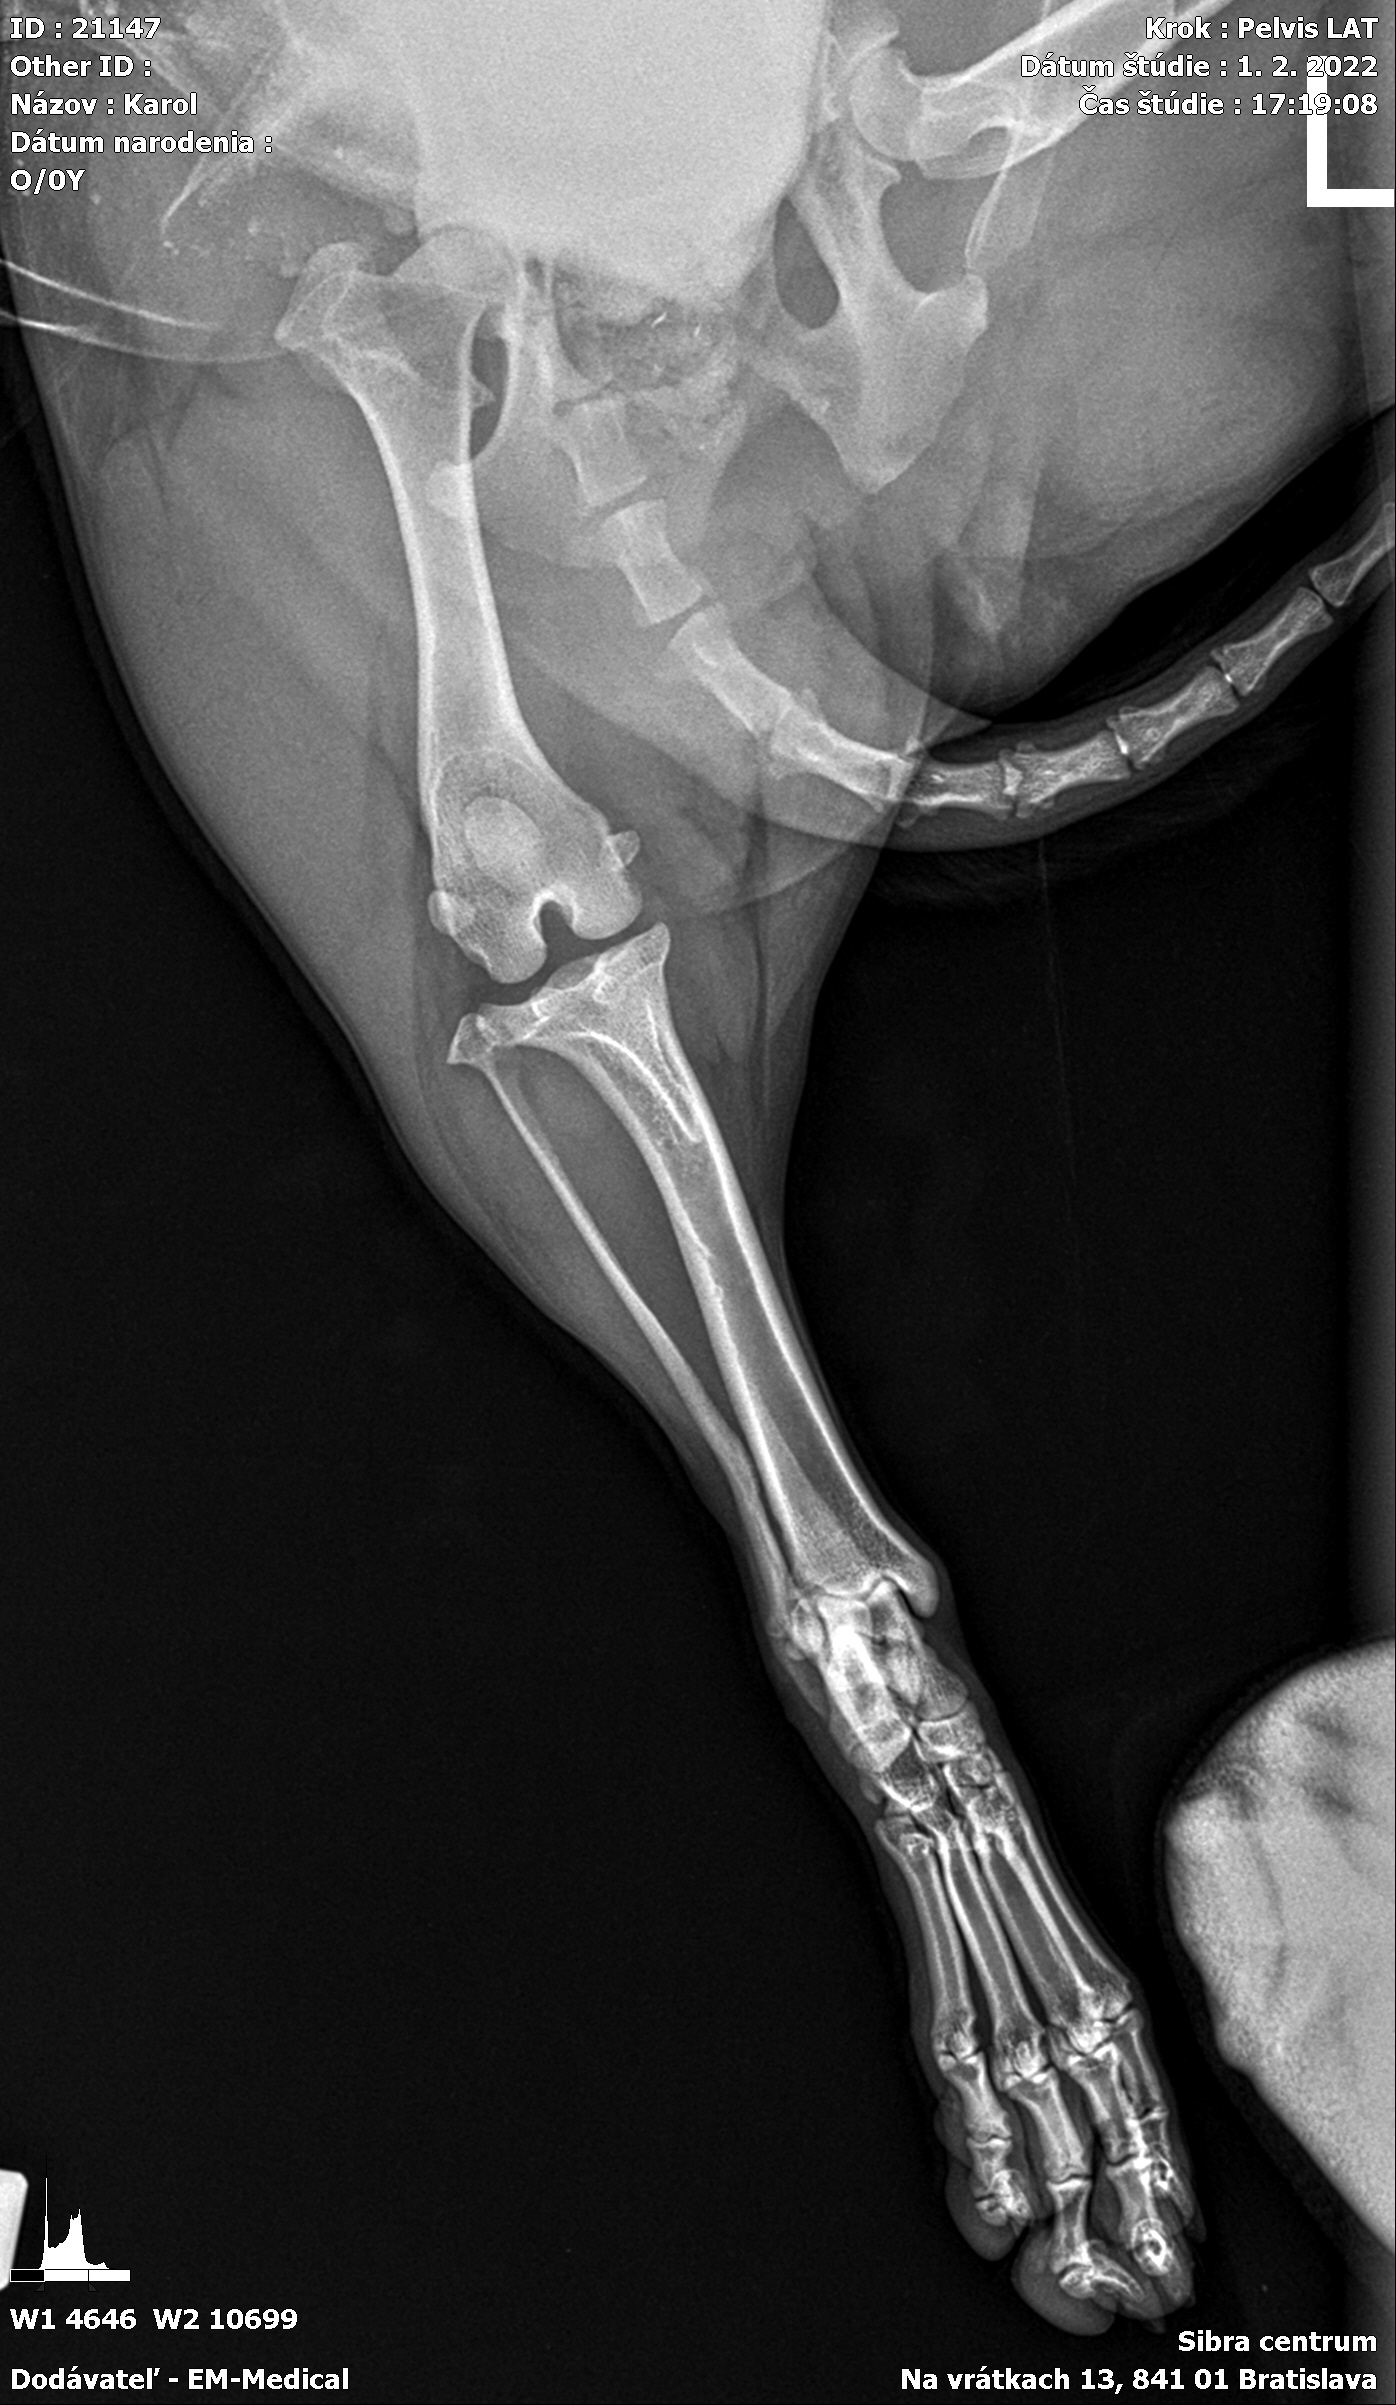

Karola nám doviezla pani, ktorá ho našla, asi jediná dobrá duša, ktorá pri ňom neprešla so zatvorenými očami. Ihneď sme s krpcom utekali na veterinu aby sa zistila závažnosť jeho zranení. Hneď pri prvých RTG snímkoch sa ukázala obojstranná fraktúra panvy, taktiež fraktúra krídla panvy a keby mu to chudákovi nestačilo, do tretice sa objavila zlomenina stavca. Karolko mal neznesiteľné bolesti, ale krásne prečkal vyšetrenie lebo vedel, že je v dobrých rukách a dostáva sa mu pomoci. Po nálezoch sme okamžite kontaktovali neurológiu a ortopédiu na veterinárnej klinike Sibra - centrum veterinárnej medicíny, kde sme dostali hneď termín na príjem.